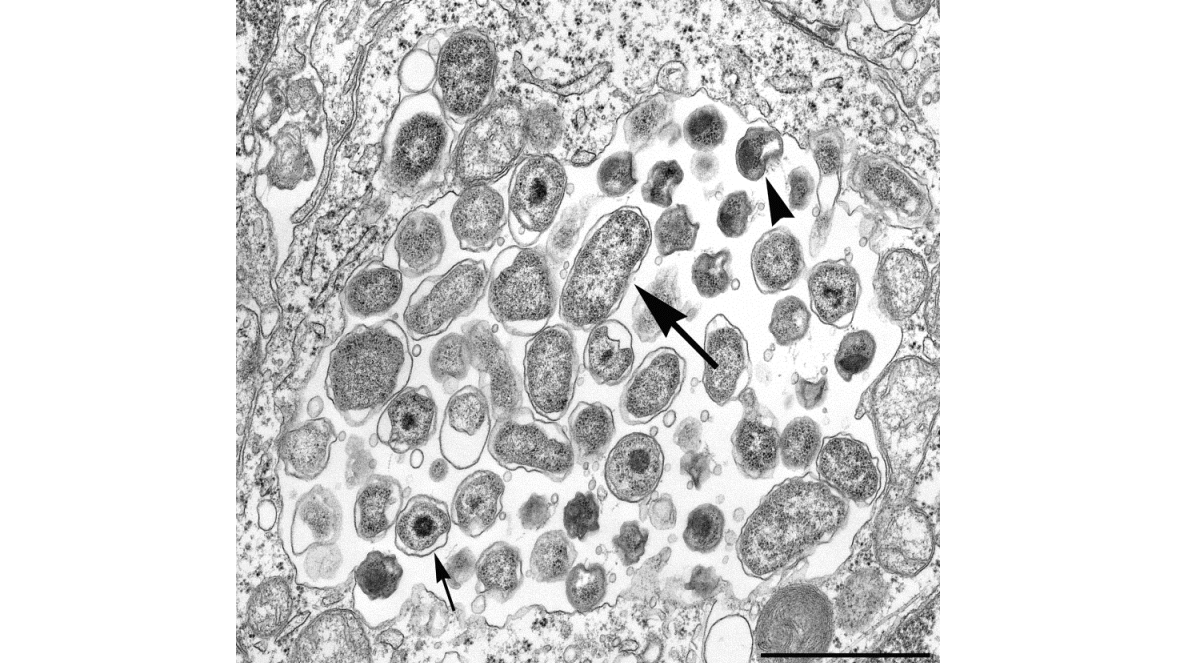

C. psittaci are intracellular gram-negative bacteria that commonly infect birds. These bacteria were previously called Chlamydophila psittaci.

C. psittaci have a unique developmental cycle with growth taking place within host cells. Laboratorians can't grow the organism using typical bacterial culture media.